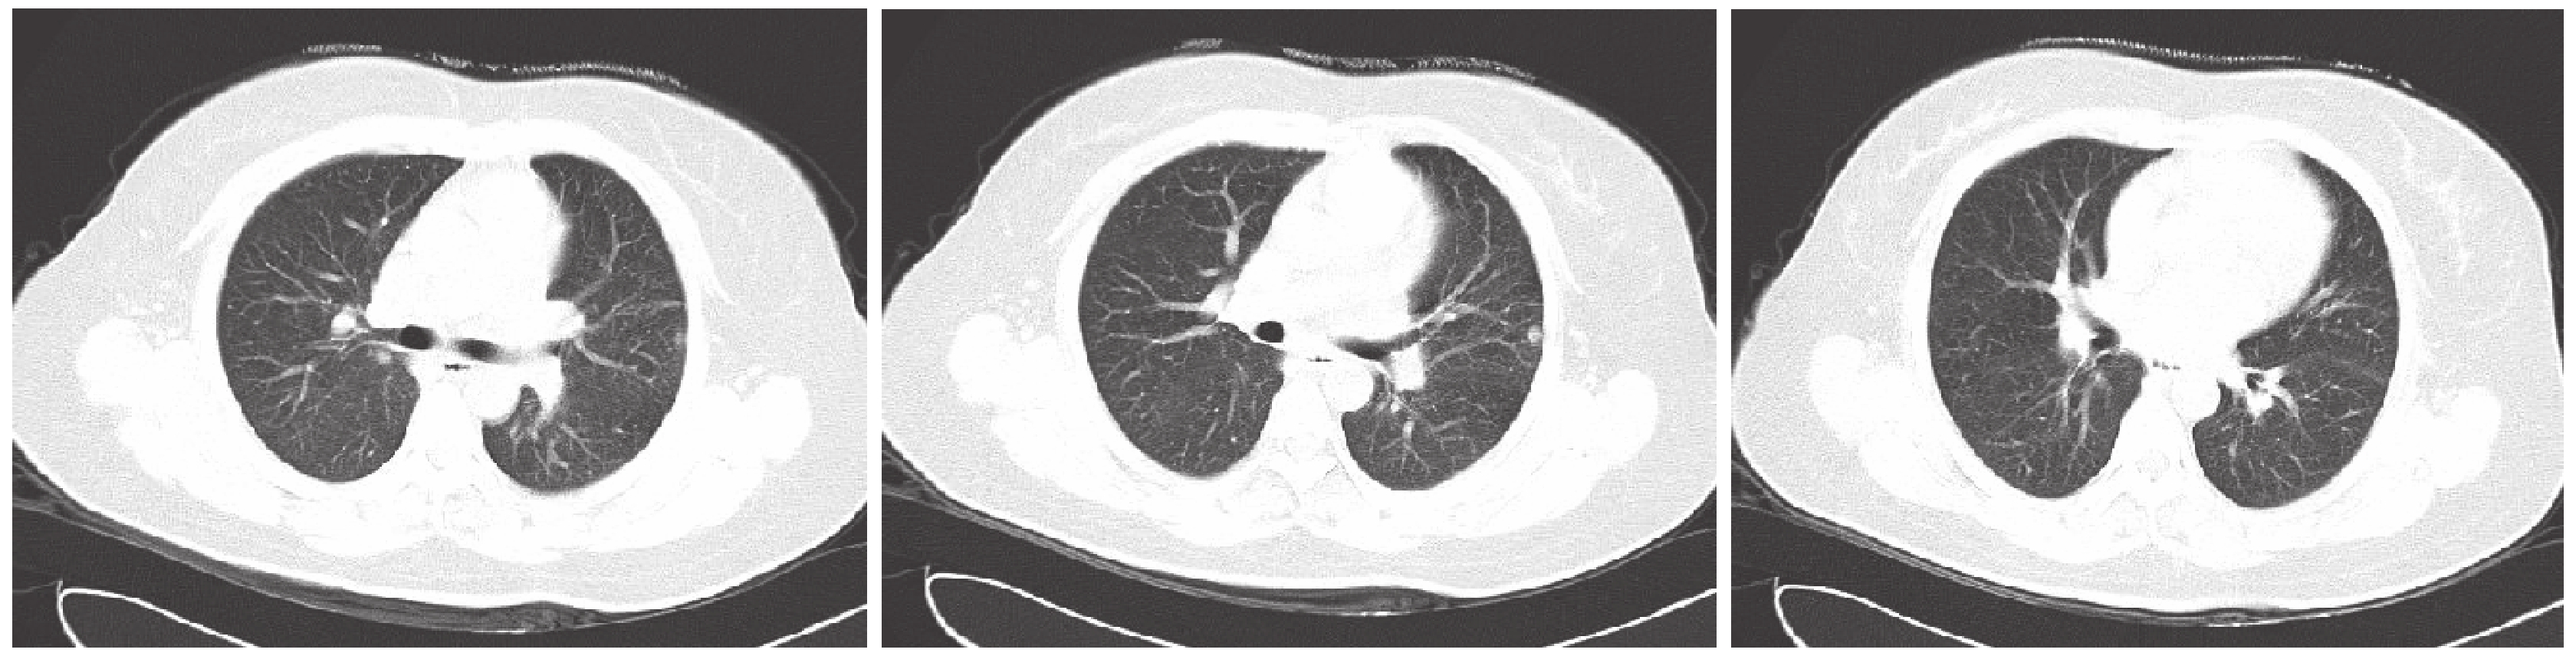

因上述癥狀持續未見好轉,患者于 2016 年 7 月 15 日再次就診于我科。查體:體溫 36.5 ℃,神清,皮膚黏膜無斑疹,全身淺表淋巴結未觸及腫大,顏面口唇及四肢紅潤,雙肺呼吸音清,兩肺未聞及干濕性啰音,心腹及四肢查體未見異常。輔助檢查:血常規、生化全項、血氣分析未見異常,女性腫瘤系列陰性,1-3-β-D 葡聚糖未見明顯異常,血沉 56 mm/1 h,C 反應蛋白 45.24 mg/L。風濕免疫系列示:補體 C4 15.4 mg/dl,免疫球蛋白 A 302 mg/dl,免疫球蛋白 G 1 610 mg/dl,免疫球蛋白 M 260 mg/dl,余正常范圍。抗核抗體系列(12 項):ANA(+),雙鏈 DNA(+),抗 nRNP 抗體(+);抗核抗體(ANA)滴度( 1∶100)(+),ANA(1∶320)(+);ANA(1∶1 000)(+);ANA(1∶3 200)(+)。結核菌素實驗(++),結核桿菌特異性細胞免疫反應陽性。2016 年 7 月 16 日復查胸部 CT(圖 3),結果示:(1)兩肺多發結節灶較前增多,部分較前增大;(2)右肺中葉炎性纖維化較前未見明顯改變,右肺上葉炎性病變已吸收,左肺炎性纖維化較前未見明顯改變。為進一步明確病情,于北京協和醫院及唐山市第四醫院會診,最后確診為:(1)系統性紅斑狼瘡(systemic lupus erythematosus,SLE)肺損害;(2)肺結核;(3)B1 胸腺瘤術后。給予口服三聯抗結核藥及口服甲基潑尼松龍片(20 mg 1 次/d)+硫酸羥氯喹(0.4 g 1 次/d)。1 個月后患者咳嗽氣促及關節疼痛癥狀逐漸好轉,2016 年 11 月 28 日復查胸部 CT 提示肺部病變較前明顯好轉(圖 4)。